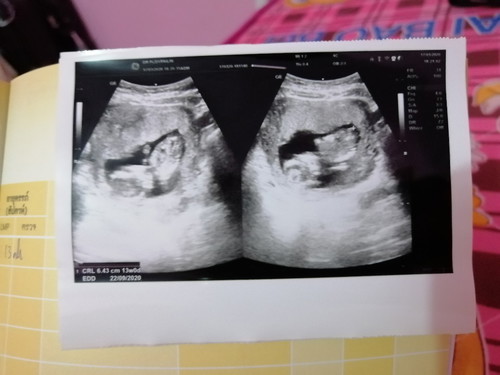

ฝากท้องแล้ว...ตอนนี้ 13 สัปดาห์ แล้วค่ะ ใครมีคำแนะนำดีๆบอกด้วยนะค่ะ

ยินดีด้วยนะคะคุณแม่ บ้านนี้ก็13สัปดาห์เหมือนกันเลยค่ะ เดี๋ยวพรุ่งนี้ไปฝากครรภ์แล้วจ้า